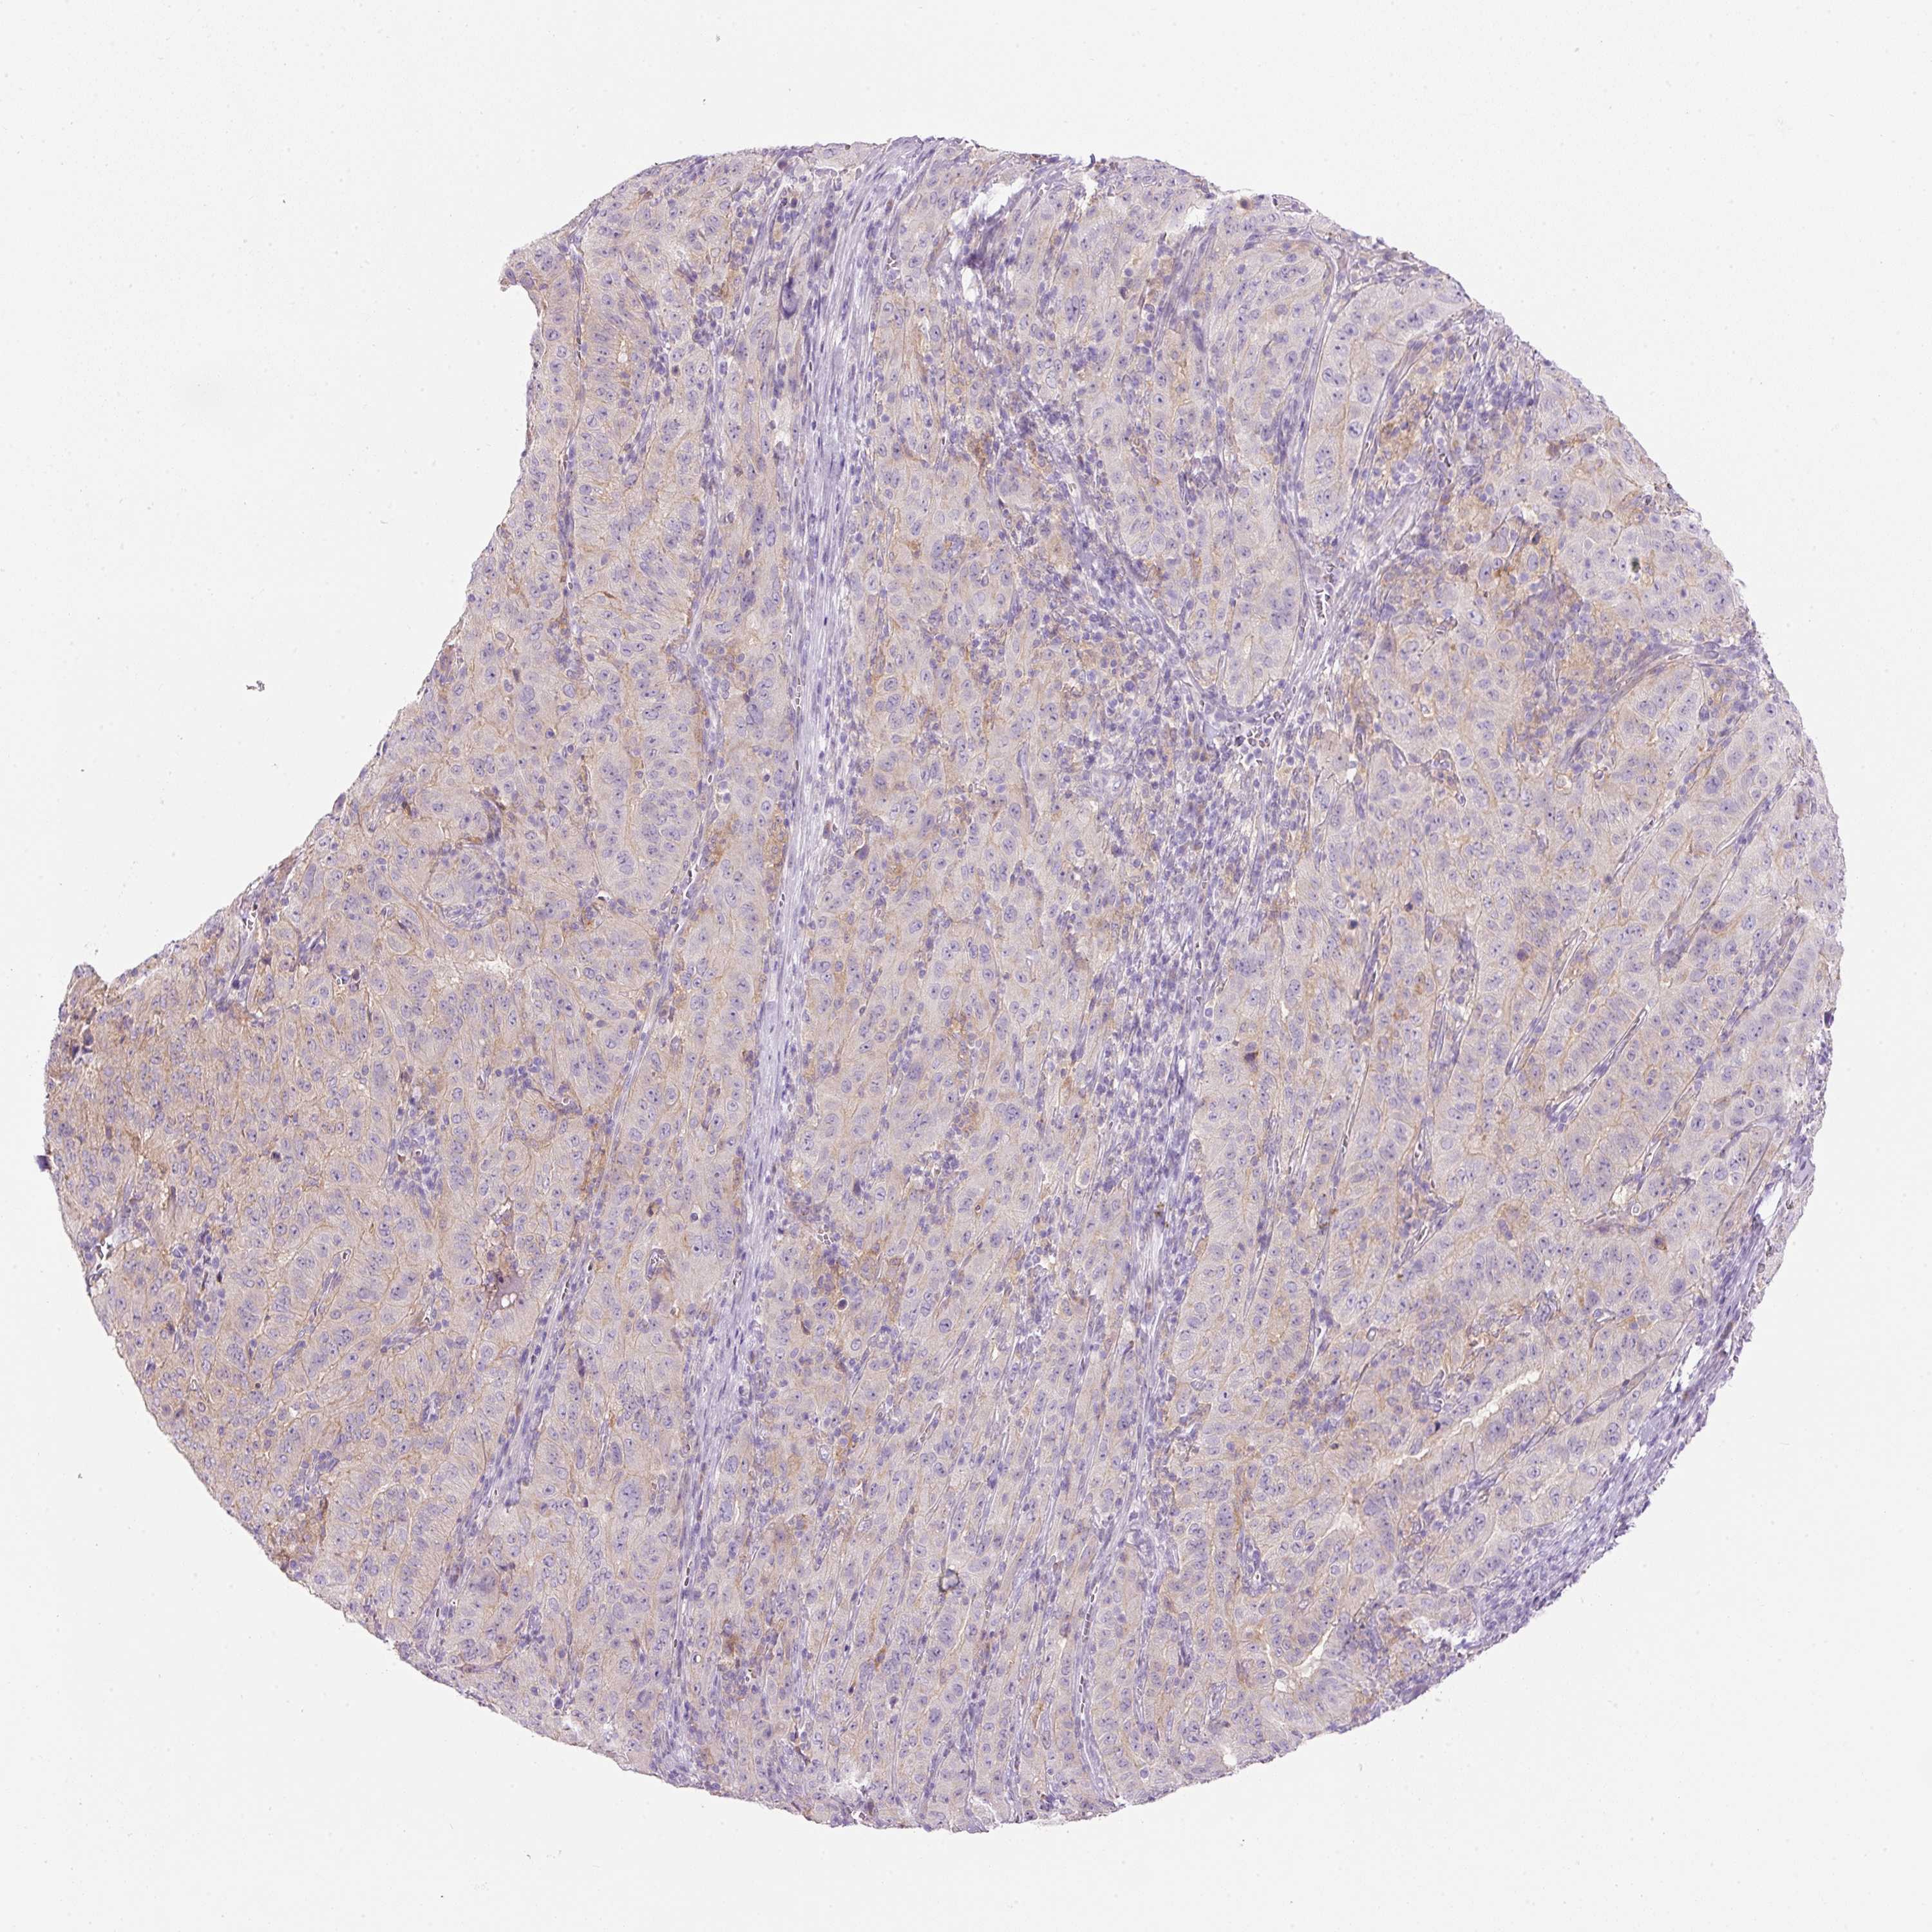

PANCREATIC CANCER - Protein expressioni

A mouse-over function shows sample information and annotation data. Click on an image to view it in a full screen mode. Samples can be filtered based on level of antibody staining by selecting one or several of the following categories: high, medium, low and not detected. The assay and annotation is described here.

Note that samples used for immunohistochemistry by the Human Protein Atlas do not correspond to samples in the TCGA dataset.

Antibody stainingi

Antibody staining in the annotated cell types in the current human tissue is reported as not detected, low, medium, or high, based on conventional immunohistochemistry profiling in selected tissues. This score is based on the combination of the staining intensity and fraction of stained cells.

Each image is clickable and will lead to virtual microscopy that enables deeper exploration of all samples and also displays staining intensity scores, fraction scores and subcellular localization as well as patient and tissue information for each sample.

Antibody HPA030875

Antibody CAB004023

Staining

High

Medium

Low

Not detected

Intensity

Strong

Moderate

Weak

Negative

Quantity

>75%

75%-25%

<25%

None

Location

Nuclear

Cytoplasmic/membranous

Cytoplasmic/membranous,nuclear

Adenocarcinoma, NOS

Adenocarcinoma, metastatic, NOS